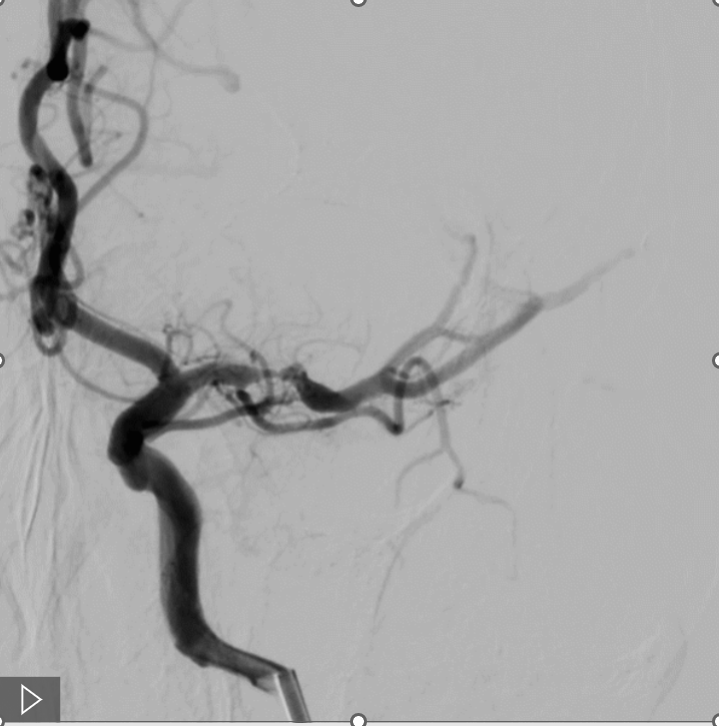

咱们来举几个病例,来详细说说它的优点,第一、定位准确,无需导丝交换,以一例左侧大脑中动脉狭窄为例(见病例1)。

微导丝配合球囊顺利通过狭窄,到达大脑中动脉M2段,无需导丝行走过远,球囊可以轻松到位(病例1B)

随后常规球囊6ATM扩张,复查造影满意后,释放4.0*23无Tip支架,术后无血管缺失。